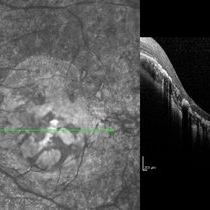

Optic Disc Drusen Optic Disc DrusenJul 10 2013 by Hamid Ahmadieh, MD SD-OCT image of the right eye of a 24-year-old woman with optic disc drusen and VA 20/20. Photographer: Solmaz Shahmohammadi, Negah Eye Center, Tehran Imaging device: Heidelberg Spectralis Condition/keywords: optic disc drusen, optical coherence tomography (OCT)